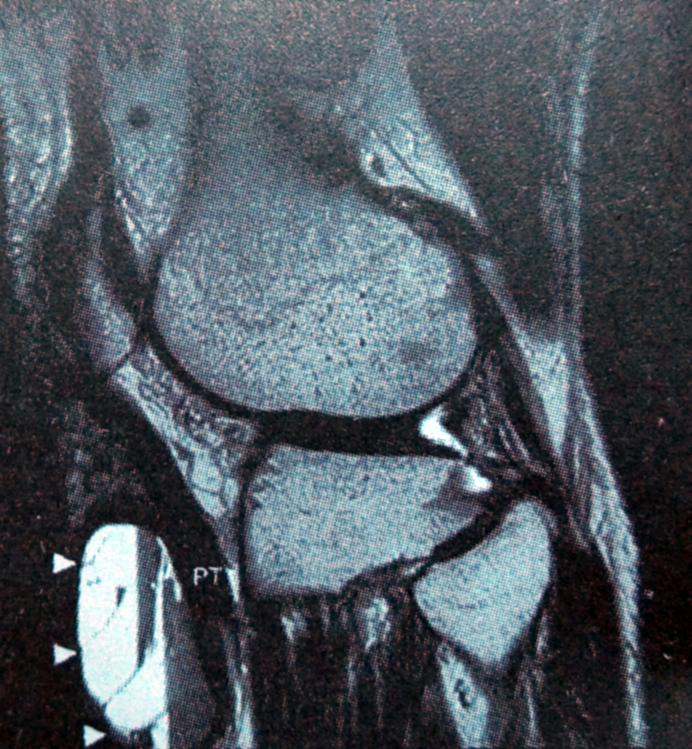

MRI表现

• 外侧半月板囊肿典型MRI表现为半月板撕裂附近的边界清楚的圆形囊肿,并见囊肿有连接部与半月板相连,可形成“吹气球征”(确诊的依据之一)。大部分伴有半月板水平撕裂和关节积液。半月板撕裂在T2WI上可看见半月板内高信号的液体;

• 在 T1WI上呈均匀的低信号,在 T2WI上呈均匀高信号。部分可见线条状低信号分隔;

• 但当半月板囊肿内有血性或凝胶状液体,蛋白含量增多时,在 T1WI 上信号强度可能有所变化,呈中等或高信号;

• 按其发生所在的部位分为半月板内型囊肿、半月板旁型囊肿、滑膜囊肿,以半月板旁型囊肿常见,发生于外侧半月板的囊肿较内侧半月板多。